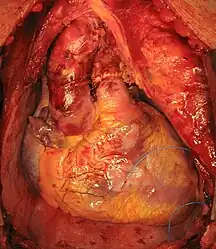

Transplanted heart in the thorax of recipient

Transplanted heart in the thorax of recipient